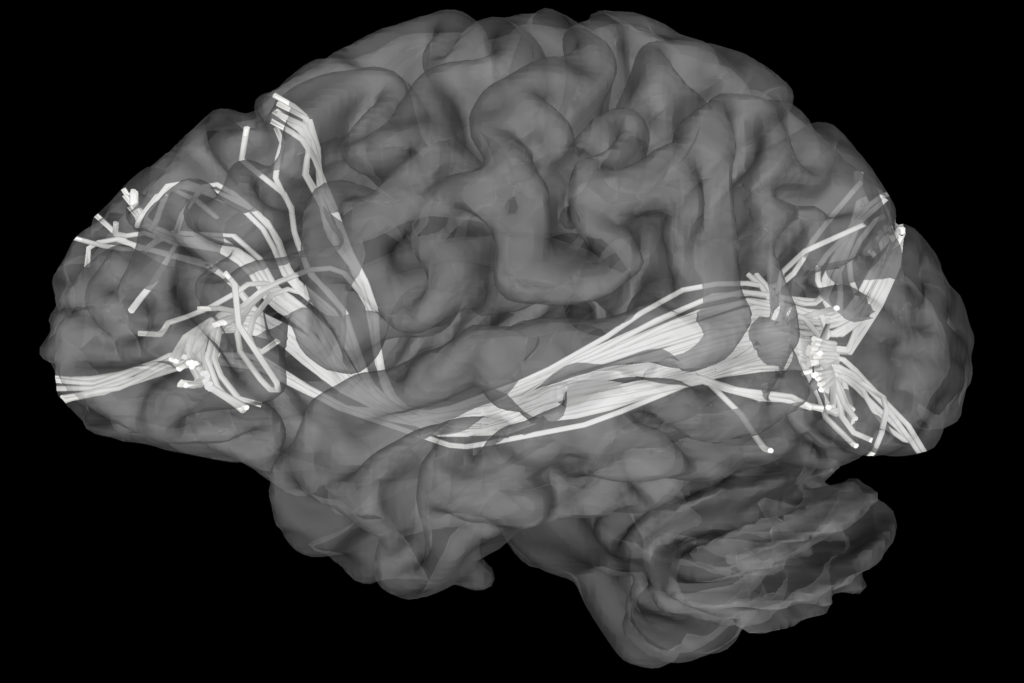

MR Tractography (Magnetic Resonance Tractography) is a specialized imaging technique that uses magnetic resonance imaging (MRI) to visualize the white matter tracts in the brain, which are responsible for transmitting information between different regions of the brain. This technique provides a 3D map of the brain’s neural pathways—such as the corticospinal tract, corpus callosum, and optic radiation—by detecting the orientation and direction of water diffusion along the nerve fibers. This allows clinicians to see and track the fibers that make up these pathways in high detail, providing an understanding of how different regions of the brain communicate with each other.

MR Tractography offers a high-resolution, non-invasive method for visualizing the white matter tracts that are essential for brain function. This allows neurosurgeons to map complex neural networks with high precision, providing them with detailed anatomical information that is critical for planning surgeries around functional brain areas.

MR Tractography significantly enhances preoperative planning, providing a comprehensive map of the brain’s white matter. This 3D mapping helps the surgeon visualize the spatial relationship between tumors, vascular malformations, and important brain tracts, ultimately improving surgical precision and reducing the likelihood of inadvertent damage to critical structures.